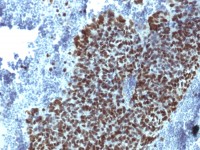

IHC-P analysis of lung cancer tissue (left) and human rectum tissue (right) using GTX82798 KLF4 antibody [1E5].